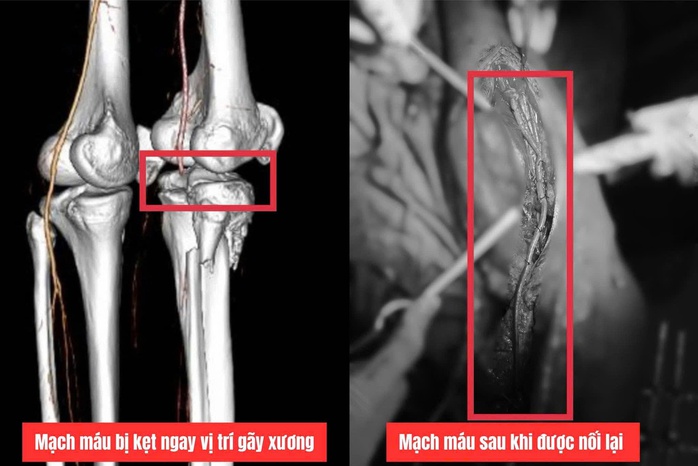

Qua kiểm tra, bác sĩ phát hiện mạch máu chi dưới mất tín hiệu động mạch khoeo và động mạch chày trước, tiên lượng nguy cơ cao cắt cụt chân, nhiễm độc toàn thân do thiếu máu chân kéo dài.

Sau đó, ê-kíp quyết định thực hiện phẫu thuật bắc cầu mạch máu để tái lập dòng chảy cho chi dưới.

Các y bác sĩ đã lấy đoạn tĩnh mạch chân trái dài khoảng 40cm để làm cầu nối, thay thế cho đoạn động mạch khoeo bị tổn thương, tái thông dòng máu từ đùi xuống cẳng chân và đã thành công.